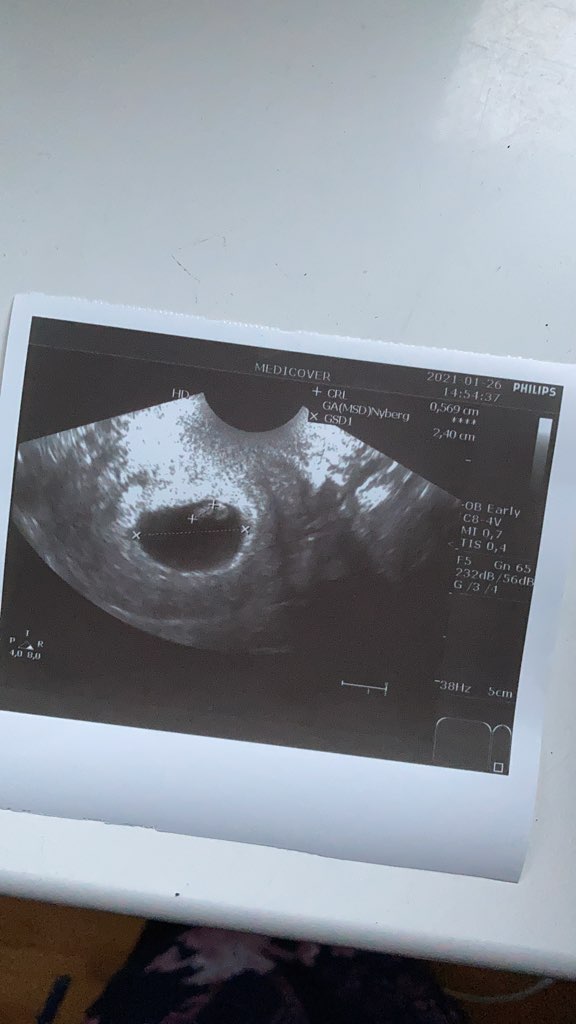

6+2 dzisiaj, widziałam bijące serduszko jednak lekarka powiedziała, że nic nie bedzie jeszcze słychać wiec ta przyjemność jeszcze przede mną :-)

Poryczalam sie w toalecie jak sie ubierałam po badaniu bo nie wierzyłam do tej pory, że tam jest człowiek 😂 w tydzien z 1.8 mm urósł do 0.56mm 🥺

Co do plamienia powiedziała, ze faktycznie coś na szyjce widzi jakaś krew ale sprawdziła jajniki, macice, malucha i mowi ze wszystko okej. Nie panikować (powtórzyła głównie to co lekarz ostatnio - póki to nie żywa krew i duża jej ilość nie nakręcać się a po dupku powinna się sytuacja poprawic:-))

Z wrażenia nie dodałam zdjęcia! 😂

• IMG_0929.jpg